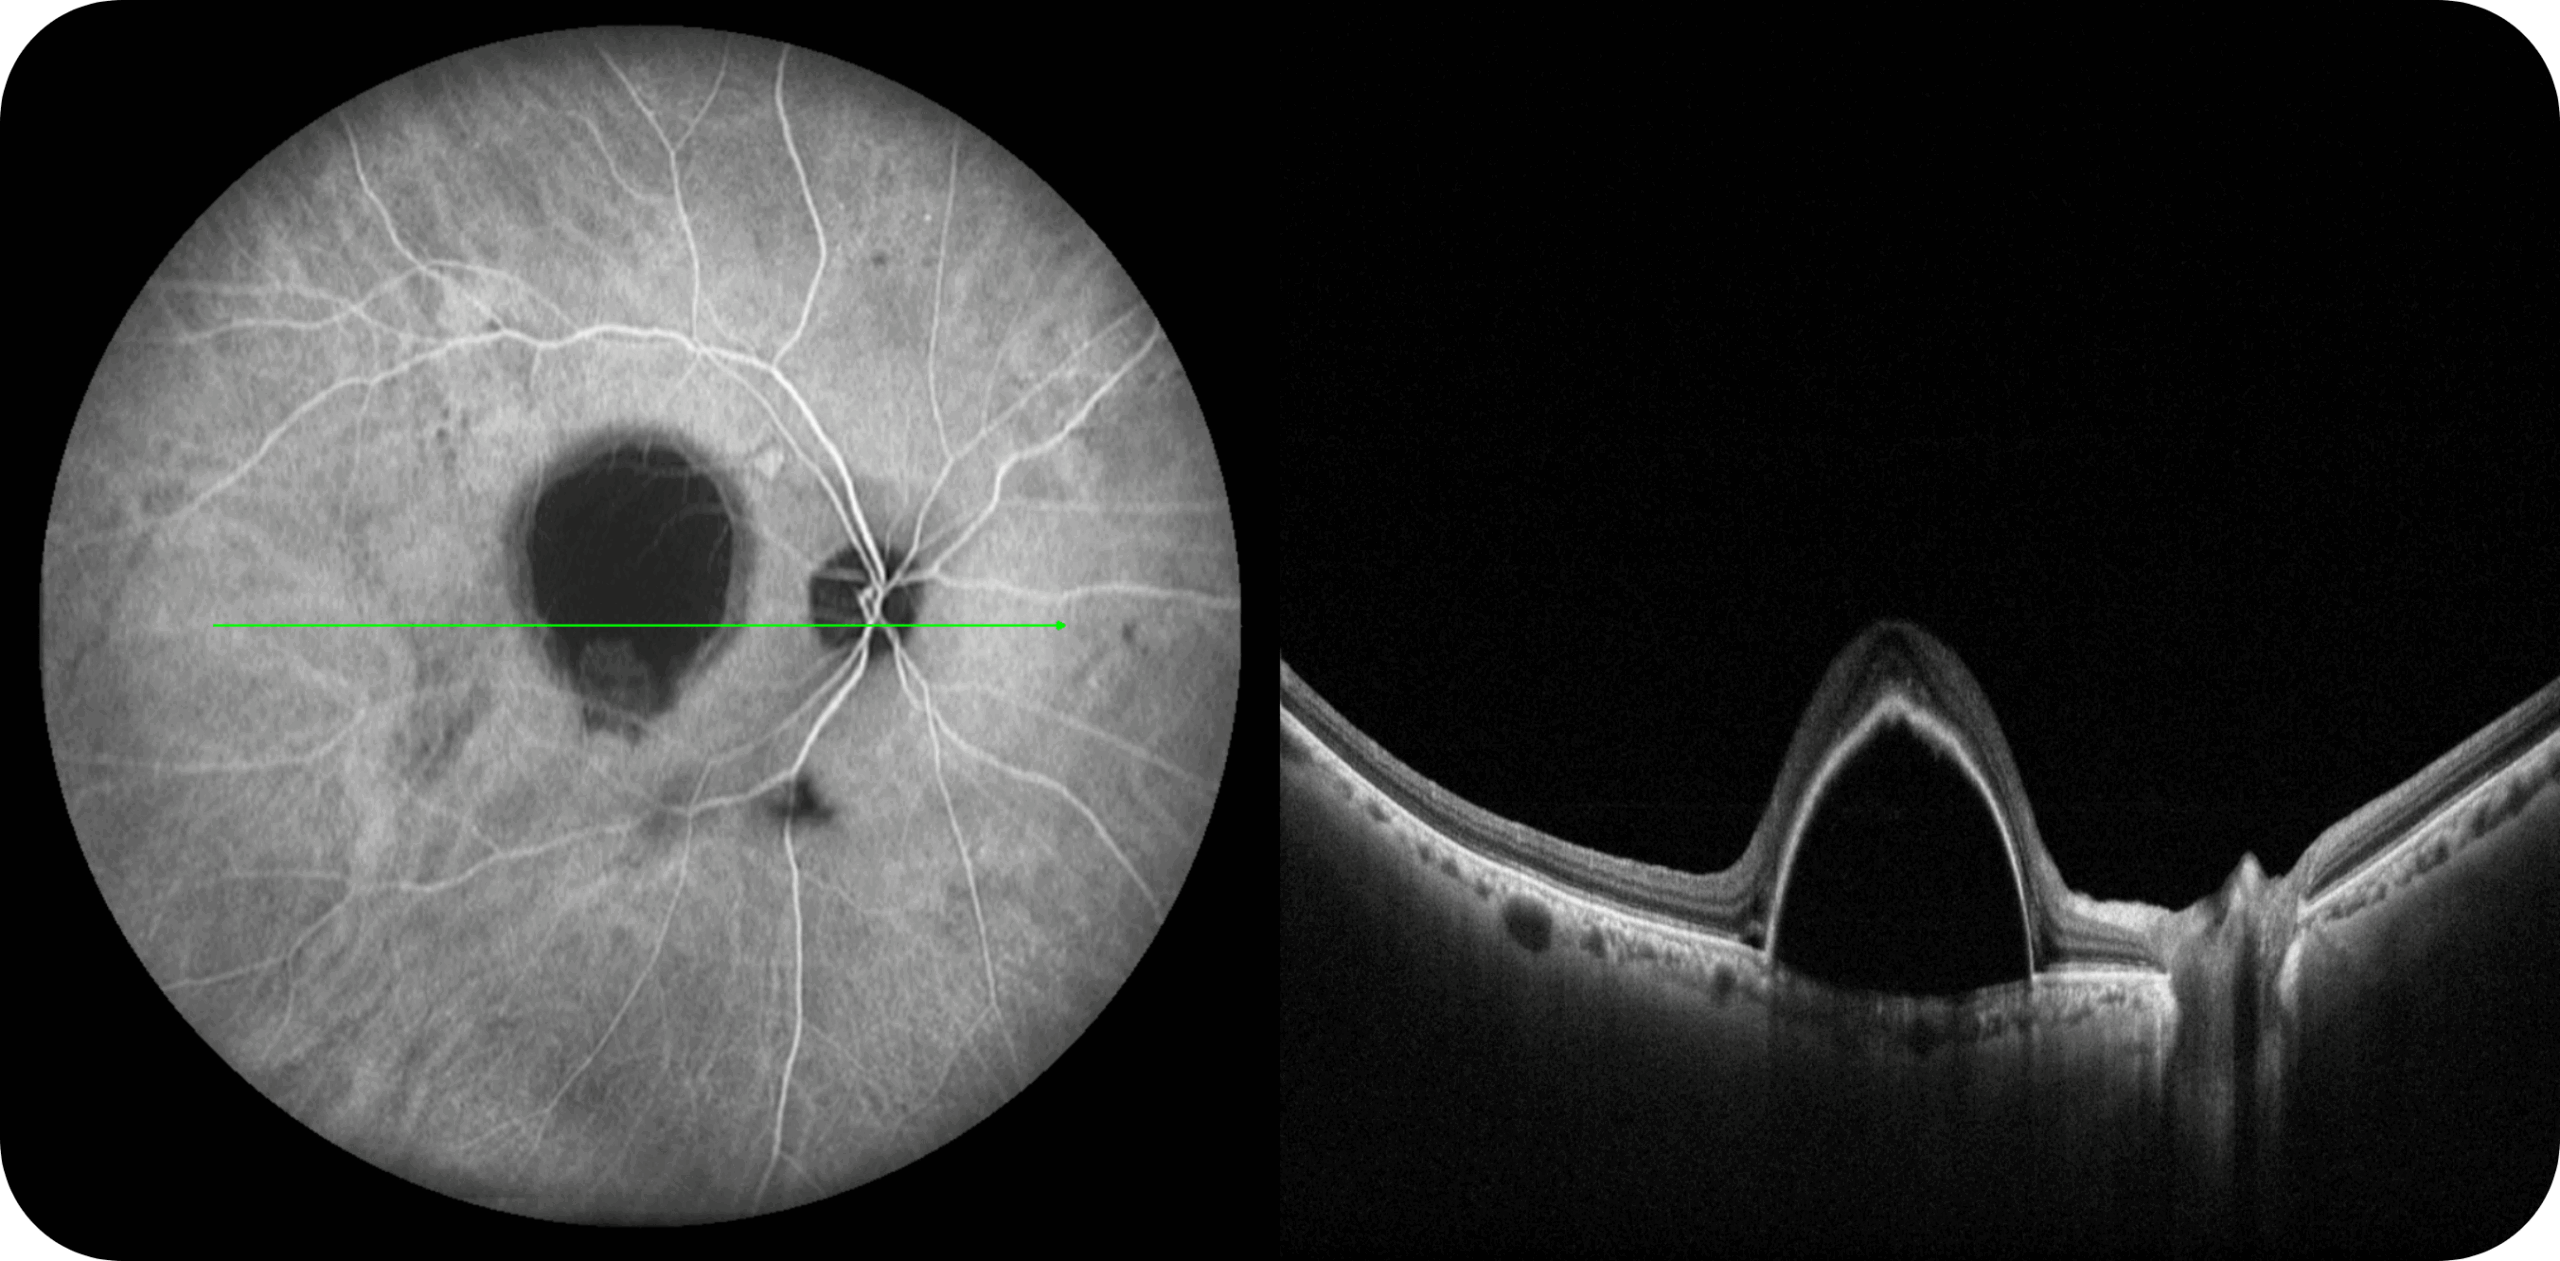

Uma única varredura pode obter rapidamente imagens sincronizadas de imagens coloridas de campo ultralargo/FAF/FFA/ICGA e SS-OCT, alcançando sincronização em tempo real e alinhamento preciso de imagens planas e estruturais da retina, melhorando significativamente a eficiência da inspeção e otimizando o processo de diagnóstico e tratamento.” Uma única varredura pode obter rapidamente imagens sincronizadas de imagens coloridas de campo ultralargo/FAF/FFA/ICGA e SS-OCT, alcançando sincronização em tempo real e alinhamento preciso de imagens planas e estruturais da retina, melhorando significativamente a eficiência da inspeção e otimizando o processo de diagnóstico e tratamento.

Multi-Modalidade

Altamente integrado com tecnologias como SLO confocal e SS-OCT, ele combina imagens coloridas SLO de campo ultralargo, angiografia confocal a laser, autofluorescência e imagens tomográficas de segmento anterior e posterior ultraamplas e profundas em um único sistema.

Retinopatia diabética, degeneração macular e outras doenças da retina.

Estudo da coroide em casos complexos.

OCTA até 220° em mosaico, para análise detalhada da vascularização.